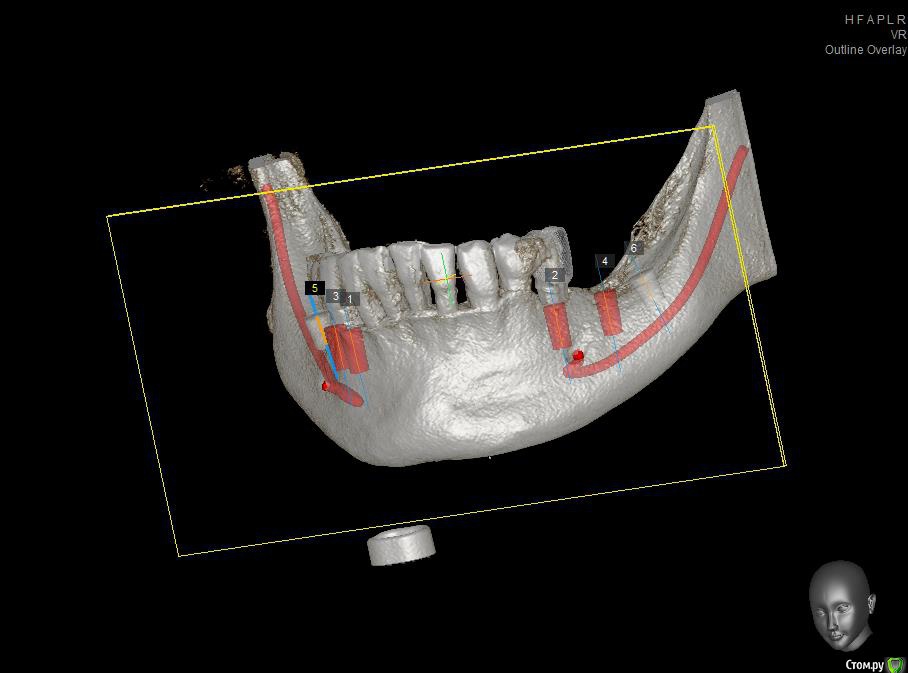

Павел7809 Опубликовано 17 сентября, 2015 Автор Поделиться Опубликовано 17 сентября, 2015 Продолжаю делится этим случаем и выкладываю на суд возможную имплантацию.1 Сначала будет удаление 5 ок с изготовлением иммедиат протеза2 Потом перевод иммедиат протеза в рентгенконтрастную модель и отправка на кт с ним( через 2 месяца после удаления)3 Имплантация по шаблону, причем на место 7 ок планирую поставить короткие альфа био....как то то так....будут какие нибуди рекомендации? Ссылка на комментарий